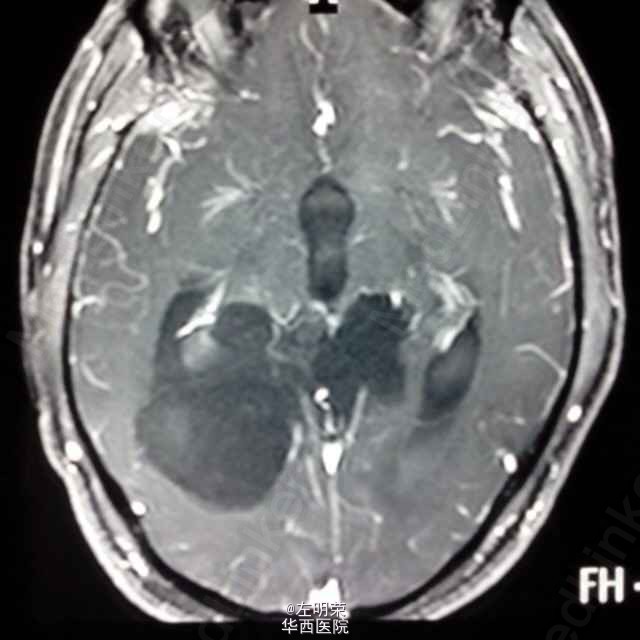

中年男性患者,“反复头痛一年”入院。查体未见明显异常;头部MRI示:松果体区占位,梗阻性脑积水。术中见病变位于右侧脑室三角区,病变范围广泛,侵及丘脑,脑干背侧,松果体区,呈白色珍珠状,质脆,切除过程中出血少,有白色坚韧包膜,予以全切,患者术后恢复良好;病理结果:松果体区表皮样囊肿。